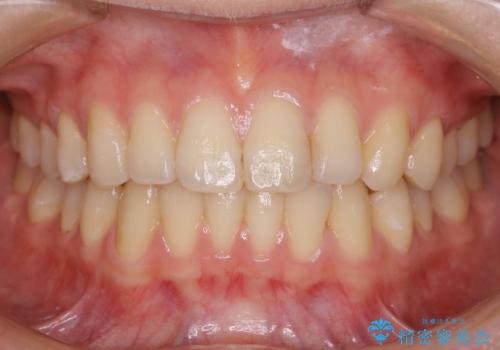

非抜歯でも劇的変化 インビザライン矯正治療

- 前歯のガタつきと噛み合わせの改善を主訴に初診来院され、審査の結果マウスピース装置による非抜歯での矯正を行うこととなりました。

元々の顎骨や口腔・歯槽骨が小さく、どうしても歯が並びきらない状況になっていました。マイクロインプラントという固定源からゴムかけを行うなど、補助装置を活用しながら臼歯部を順番に遠心方向(奥)に移動させていくことで抜歯をしなくても歯が並ぶよう計画を立てました。

歯のガタつきを治すため矯正治療を希望。審査の結果、非抜歯での矯正が可能であるという見通しが立ったためインビザラインによる非抜歯矯正治療を行った。